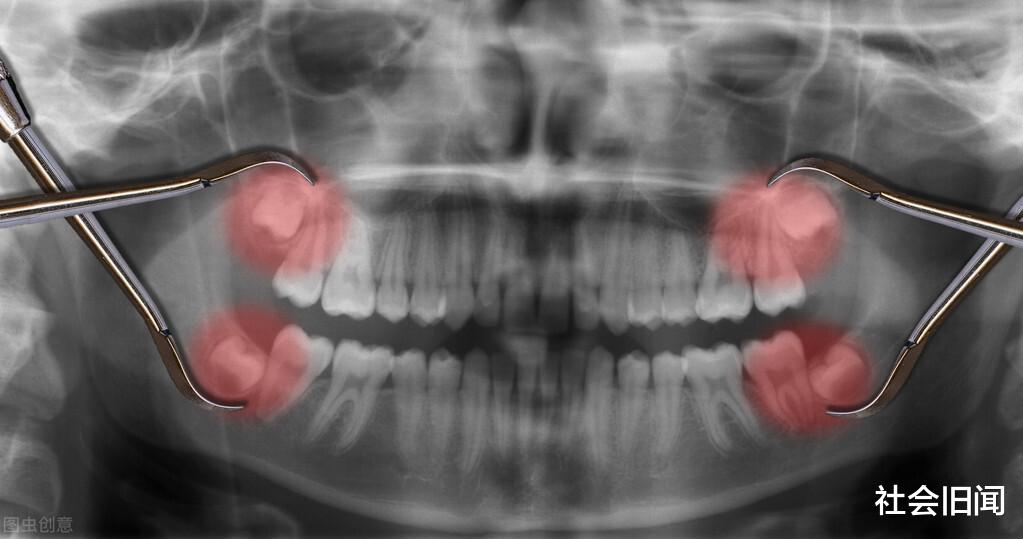

正因为是这样 , 所以猿类最终进化为人类 , 不过在进化的过程中 , 既然出现了5处不完美的地方 , 第一个不完美的地方就是智齿 , 可能很多朋友有智齿 , 一般智齿出现的年龄是在16到30岁之间 , 智齿不仅没有给人类带来智慧 , 反而给人类带来了很多麻烦 , 智齿非常容易蛀牙 , 一旦蛀牙之后就会很疼 , 一般医生都建议拔掉智齿 , 所以智齿对于人类来说没有好处竟是坏处 , 第二个不完美的地方是气管 , 气管和食道是人体最重要的两个器官 , 我们在呼吸的时候和吃饭的时候都要用到它们 。